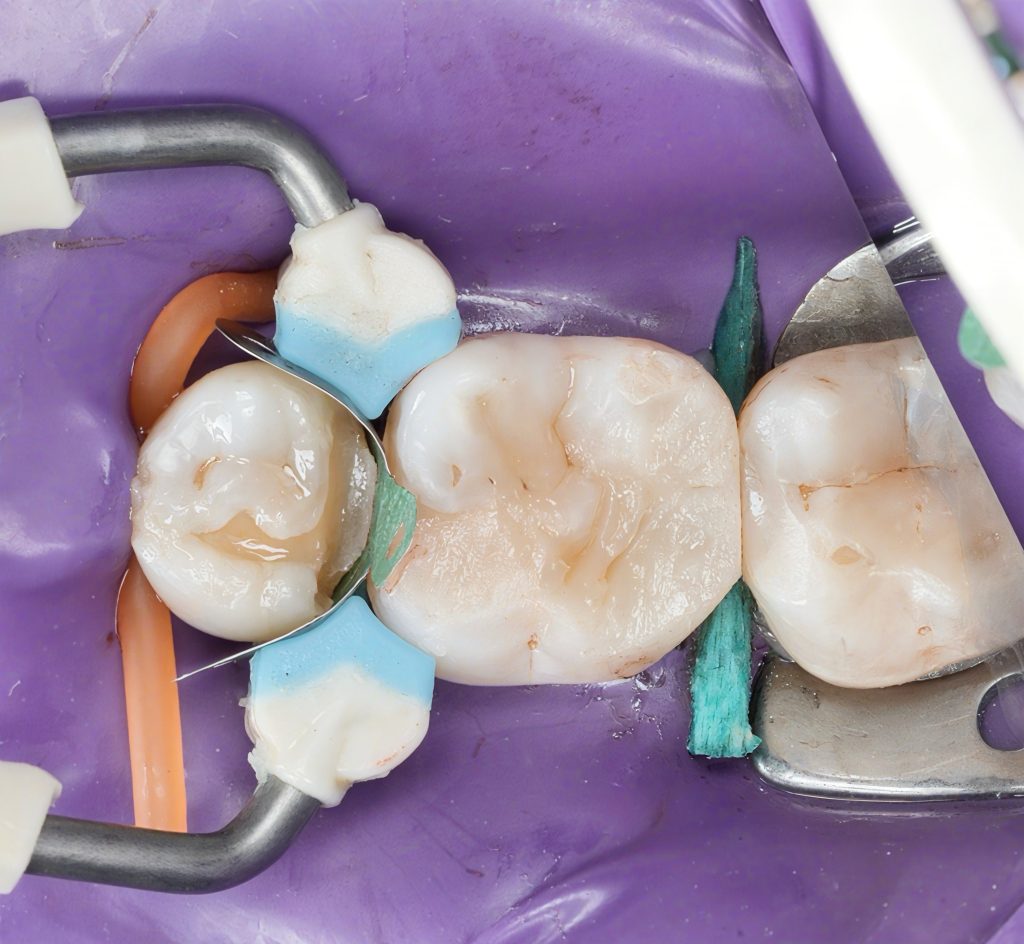

Image 4:

“Rubber dam isolation achieved using sectional clamp. Cavities visible under magnification.”

Image 5–6:

“Sectional matrices placed with wooden wedges for controlled separation and optimal gingival adaptation.”